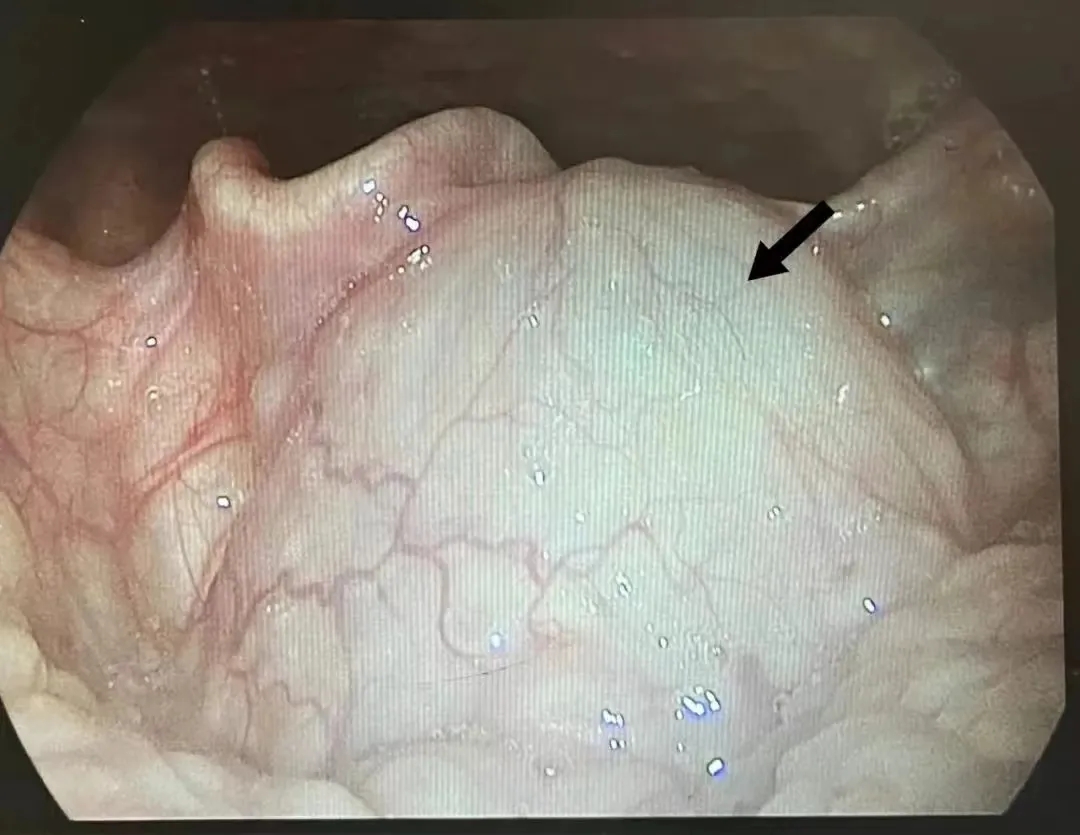

患者范某某,入院前2周自觉吞咽异物感,睡眠时偶感呼吸不畅,无吞咽困难,无咽喉部疼痛,无喘息及呼吸困难等症。在外院行电子喉镜检查后,发现舌根部有一个鹌鹑蛋大小的囊肿,位置较深,手术有一定难度。和济医院耳鼻咽喉头颈外科主任任何贤接诊检查后,考虑为甲状舌管囊肿(口内型),建议住院手术切除囊肿。

甲状舌管囊肿多见于1—10岁的儿童,亦可见于成年人。囊肿可发生于颈正中线,自舌盲孔至胸骨切迹间的任何部位(如上图所示),但以舌骨上下部为最常见。囊肿生长缓慢,呈圆形,临床上多如胡桃大,位于颈正中部位,有时微偏一侧;质软,周界清楚,与表面皮肤及周围组织无粘连。患者多无自觉症状。甲状舌管瘘如长期不治,可发生癌变,应手术切除囊肿瘘管,而且应彻底,否则容易复发。(王芳)